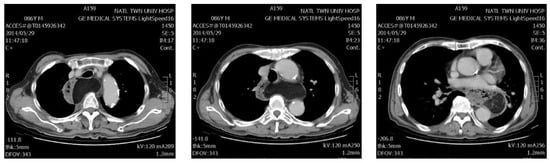

| 4 | 86/M | Lt ★ | 22 | Dysphagia | Lipoma | 151 | 12 |

| 16 | 67/M | Lt ★ | 10 | Dysphagia | GIST ◆ | 241 * | 53 |